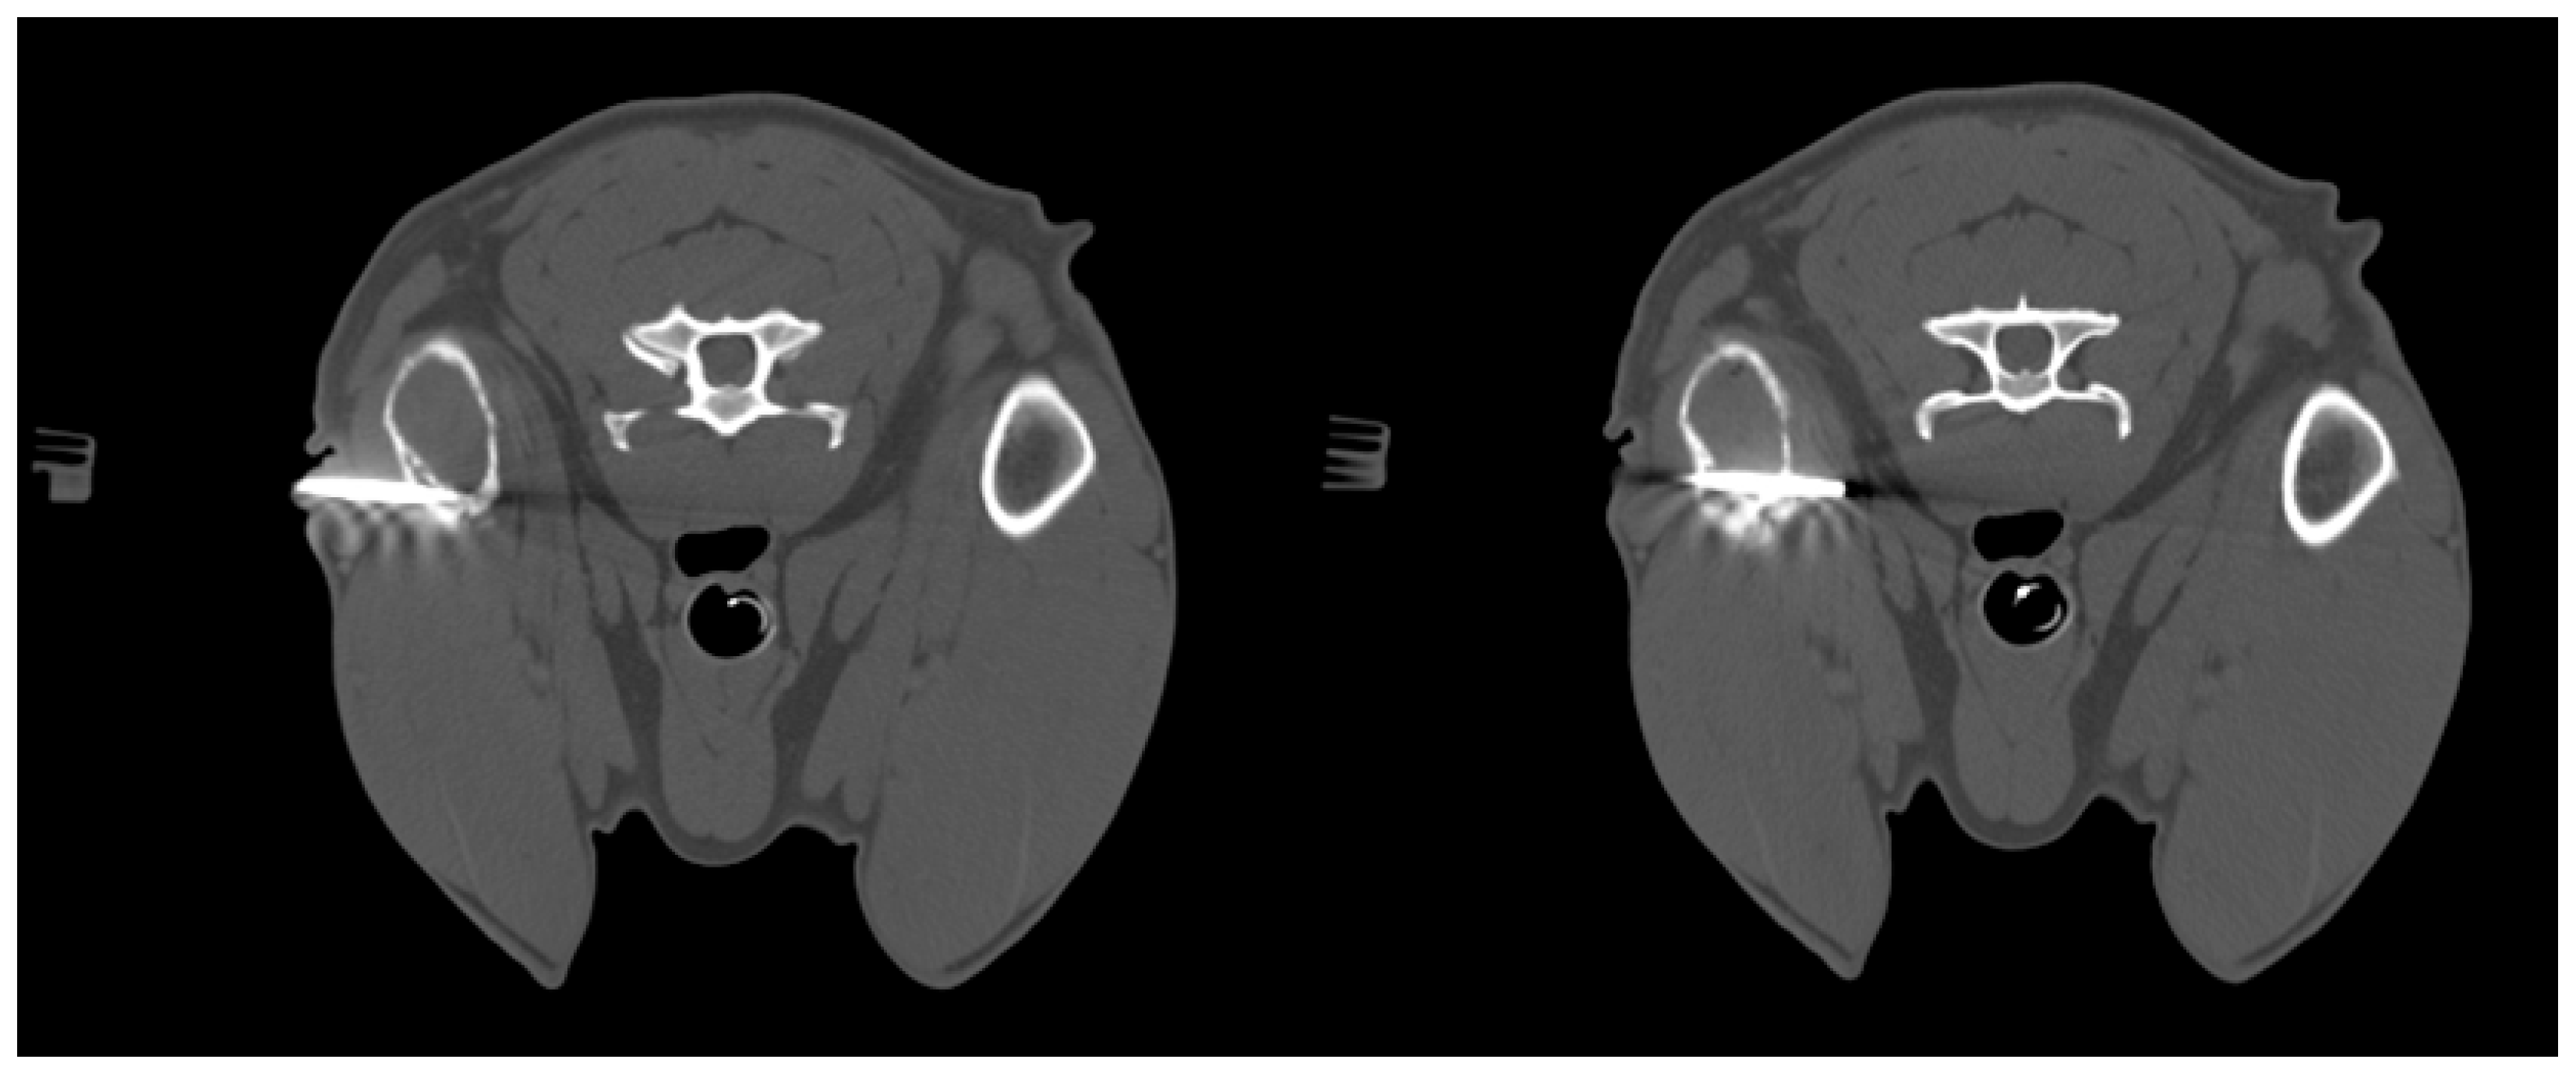

The patients included in the study underwent imaging-guided biopsies, specifically under US or CT guidance, of the masses under examination as shown in Figure 1 and Figure 2. Biopsy samples were collected using a semi-automatic spring-loaded tru-cut (14 G) in the case of soft tissue lesions and a bone needle (8–10 G) for bone tissue. These interventional diagnostic methods were performed after monitoring and anesthetizing the patient, under the continuous supervision of the anesthetist in charge. Trichotomy of the area of interest was performed, followed by surgical scrubbing with betadine and alcohol. Once the patient was prepared, a small incision was made with a number 11 scalpel blade on the skin surface, through which the tru-cut (14 G) or bone needle (8–10 G) was subsequently inserted. The biopsies were performed using ultrasound guidance or computed tomography, depending on the case, the location of the lesion and the availability of instruments.

Figure 2. Dog, Mixed breed, 13 y, spayed female. Phases of CT-guided humeral biopsy with bone window. Final diagnosis: humeral osteosarcoma.